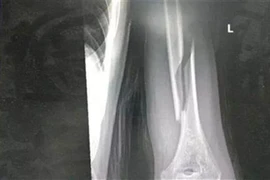

1 tuần 3 trường hợp gãy xương cánh tay từ trò chơi vật tay

Có những trường hợp nhập viện trong tình trạng gãy nham nhở, khó đưa xương về vị trí ban đầu, tổn thương các dây thần kinh quay, trụ và mạch máu lân cận.

Trong lúc thi vật tay cùng bạn bè, nam thanh niên 18 tuổi bất ngờ nghe thấy một tiếng “rắc” vang lên, kèm theo cảm giác đau dữ dội.